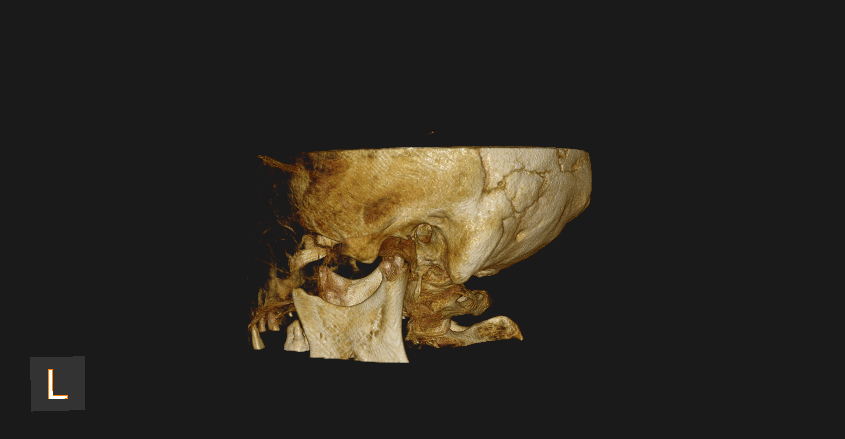

Cone Beam Computed Tomography (CBCT)

Special 3D imaging technique that provides detailed images of teeth, jaws, nerves, and surrounding structures. CBCT is quick, accurate, and offers 3 Dimensional knowledge compared to normal X-rays, ensuring better care for complex dental issues.

Accurate diagnostic features of various pathologies like cysts and tumors for better treatment planning